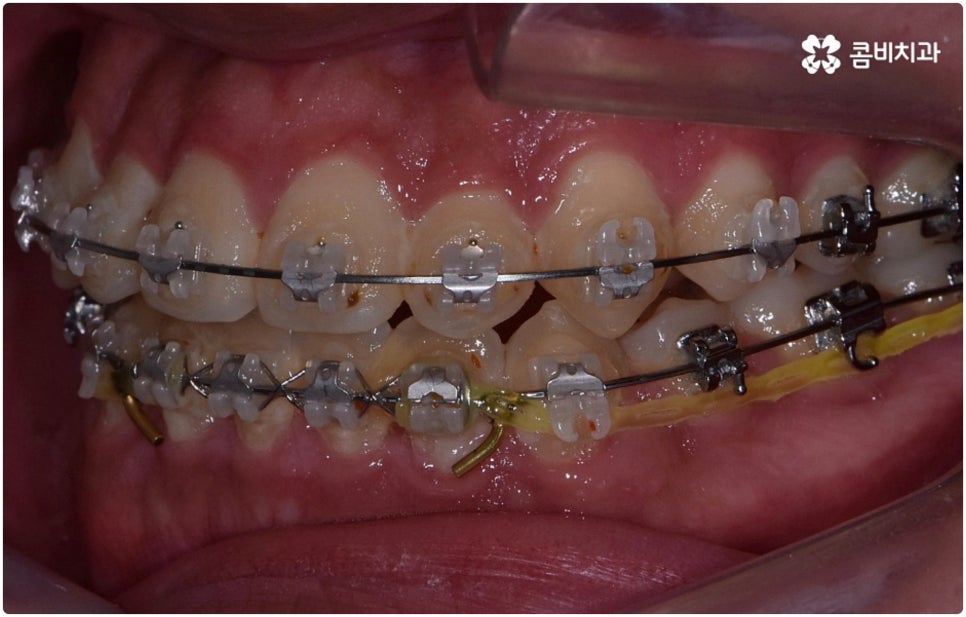

부정교합은 부정교합 1급, 부정교합 2급, 부정교합 3급 이렇게 세가지 종류로 나눌 수 있는데요. 부정교합 1급은 이를 다물었을 때 위아래 어금니는 잘 맞물리지만 덧니가 있거나 치아 사이가 살짝 벌어져 있는 경우처럼 치열이 삐뚤어진 경우를 말하는 것으로 골격이나 구조적인 부분에는 크게 문제가 없기 때문에 정도가 심하지 않다면 보다 빠르고 간편한 교정 치료가 가능한 케이스라고 할 수 있어요. 부정교합 2급은 상악이 하악보다 더 튀어나온 상태로 위에서 언급했던 무턱, 돌출입이 여기에 속하며 반대로 부정교합 3급 은 주걱턱처럼 하악이 상악보다 튀어나온 상태를 의미하고 있습니다.

환자분들마다 상황은 모두 다르기 때문에 부정교합 교정 치료를 할 때는 정밀 검진 후 맞춤 치료 계획에 따라 무리하지 않게 진행하는 것이 중요한 포인트라고 할 수 있어요. 이때 구강내 상태 (치아, 잇몸, 치열, 교합 등) 뿐 아니라 구강 외 상태 (뼈의 위치 및 구조 발달, 얼굴 정면과 측면 등 안모 비율) 와 같은 모든 부분을 꼼꼼하게 촬영하고 환자의 연령 및 생활 습관 등을 종합적으로 고려하여 원인을 분석한 다음 치아를 어떻게 얼마나 움직여야할지 면밀하게 교정 플랜을 세우는 것이 필요하므로 3D CT, 모르페우스 같은 정밀 진단 기계를 갖추고 있는 치과에서 다양한 임상 경험을 통해 뛰어난 기술력을 가지고 있는 담당의 선생님께 치료 받으시길 권유드리고 있습니다.

부정교합 2급, 부정교합 3급 과 같이 구조적인 부분에 원인이 있는 문제라면 잇몸뼈가 다 굳고 난 다음인 중장년 성인분들의 경우 교정 치료를 받는 것이 과연 부정교합 개선에 효과가 있을까 궁금해 하실 수 있어요. 특히 턱관절 이상 문제는 수술을 통해서만 고칠 수 있다고 알고 계셨던 분들은 부담을 느끼고 치료를 미루셨을 수 있는데요. 물론 성인분들의 경우 상황에 따라, 예를 들어 정도가 매우 심한 부정교합 3급 케이스라면 악교정수술을 받아야 할 수도 있습니다. 또한 대부분의 부정교합 2급, 부정교합 3급 케이스들 같은 경우 초등학교 고학년에서 중학교 저학년 사이에 교정 치료를 시작하는 것이 좋다고 권유하는 것도 사실인데요, 그 이유는 아무래도 치아 이동 속도가 빠르고 전반적인 발달 상황에 맞추어 자연스럽게 치료를 진행할 수 있는 성장기의 특성상 이 시기부터 지속적으로 턱뼈 크기 부조화를 조절하고 상하악의 올바른 성장을 유도하는 게 보다 효율적이기 때문이라고 할 수 있어요.

하지만 관련 기술 발달로 교정에 있어서 적기라는 것이 크게 의미가 없어진 근래에는 정도가 많이 심각하지 않다면 중장년 성인분들의 경우에도 각자에게 맞는 교정 치료를 통해서 얼마든지 부정교합 개선이 가능하니 안될 것이라고 지레 짐작을 하여 내원을 망설이시기 보다는 먼저 교정 치료를 위한 검진을 받아보고 자신의 상황에 대해서 숙련된 의료진과 충분히 상담해 보시길 권유드리고 있습니다. 특히 수술적인 치료를 할 때도 교합을 바로잡기 위해서는 치과와 협진하여 진행하는 케이스가 많으니 교정을 통한 부정교합 개선 및 턱관절 치료 효과에 대해 크게 의구심을 가지실 필요는 없을 거예요. 상황에 따라 교정 치료만으로도 기능적 개선은 물론 균형잡힌 안모와 호감가는 인상으로의 변화가 가능한 경우가 많으니 불편함을 참고 계시지 말고 정밀 진단과 상담부터 차근차근 시작해 보시면 필요한 도움을 받아 보실 수 있어요.